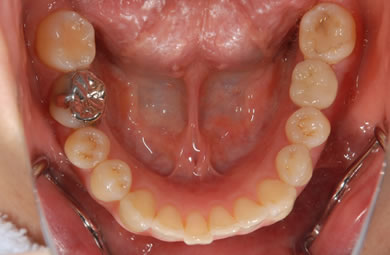

インプラント治療+セラミック治療

| 主訴 | 前歯を白くしたい。 | ||||||||||||||||||||||||||||||||

| 治療方針 | 前歯部の審美的回復をセラミック治療で行う。臼歯部の審美的・機能的回復をインプラント治療で行う。 | ||||||||||||||||||||||||||||||||

| 治療内容 | インプラント1本、メタルボンドセラミック1本、オールセラミック2本(オールセラミック用の土台2本) | ||||||||||||||||||||||||||||||||

| 総治療費 | 608,667円 | ||||||||||||||||||||||||||||||||

| 治療期間 | 4ヶ月 |